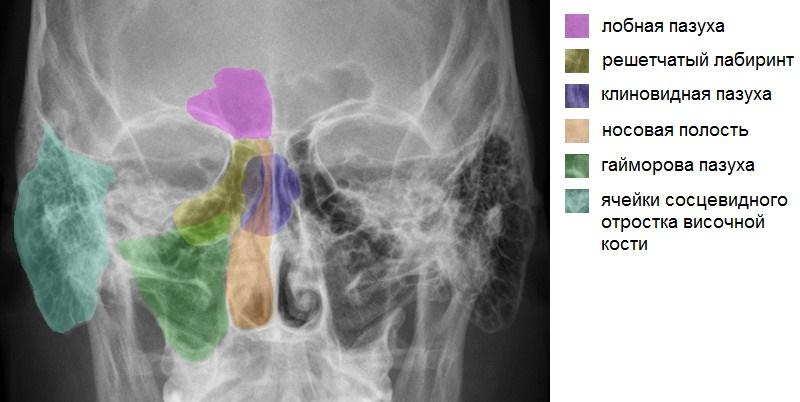

Микрорентгенография придаточных пазух носа позволяет визуализировать пневматизацию этих анатомических образований. На полученном изображении можно увидеть следующие околоносовые пазухи:

- основная;

- лобные;

- верхнечелюстные;

- решетчатые;

- сосцевидные ячейки височных костей.